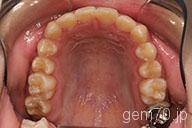

症状:叢生装置:セラミックブラケット | 非抜歯(歯を抜かない)世代:中学生

主訴)歯のでこぼこ

診断)叢生

年齢)14歳

使用装置)マルチブラケット装置

治療方法)非抜歯(歯を抜かない)

治療期間) 2年4ヵ月 通院回数 27回